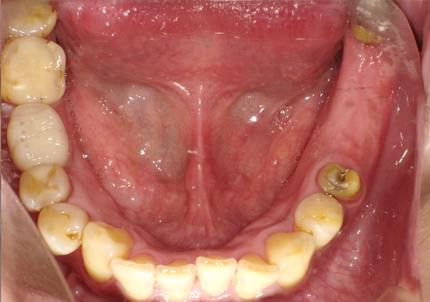

1.初診時口腔内写真(2014年6月)

3.前回治療後5年経過(2021年2月)

【左下ブリッジ5番6番歯根破折の為要抜歯】

【左下5番ソケットシールドテクニック】